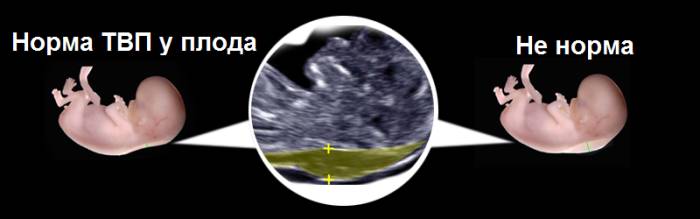

Определение толщины воротникового пространства (величина шейной складки, ТВП) — один из важнейших и довольно точных методов ранней диагностики хромосомных аномалий и других пороков развития. Именно этот эхографический маркер стал «золотым стандартом» на сроке 11—14 недель.

Потом эхографист выводит на экран верхнюю часть туловища и головку в боковой проекции, при этом в одном срезе должны быть одновременно кости и кожа спинки носа, полости 4 желудочка и кость верхней челюсти. Специалист увеличивает на мониторе область шеи. Затем измеряет наибольшую толщину скопления жидкости по задней поверхности шеи под кожей. Жидкость на экране окрашена черным цветом, а кожа и мягкие ткани — белым. После измерений врач сравнивает полученный результат с нормами.

Норма параметров

Величина ТВП сама по себе ничего не значит, это не окончательный диагноз, просто существует риск. Высокая вероятность развития хромосомной патологии подкрепляется плохими результатами анализов крови на гормоны и при величине шейной складки более 3 мм.

Если у будущего ребенка во время УЗИ выявлено ТВП больше нормы, не стоит сразу впадать в панику, так как этому может быть много причин, в том числе и совершенно здоровое его состояние.

- 12 недель. Это самый информативный этап для определения различных патологий и отклонений в развитии плода, а также течения беременности в целом. Скопление жидкости на двенадцатой неделе не должно превышать 3 миллиметров, минимальный размер составляет 0,7 мм. Важно иметь в виду, что данные могут варьироваться в зависимости от расположения головки: она может быть прижата к груди, повернута в сторону.